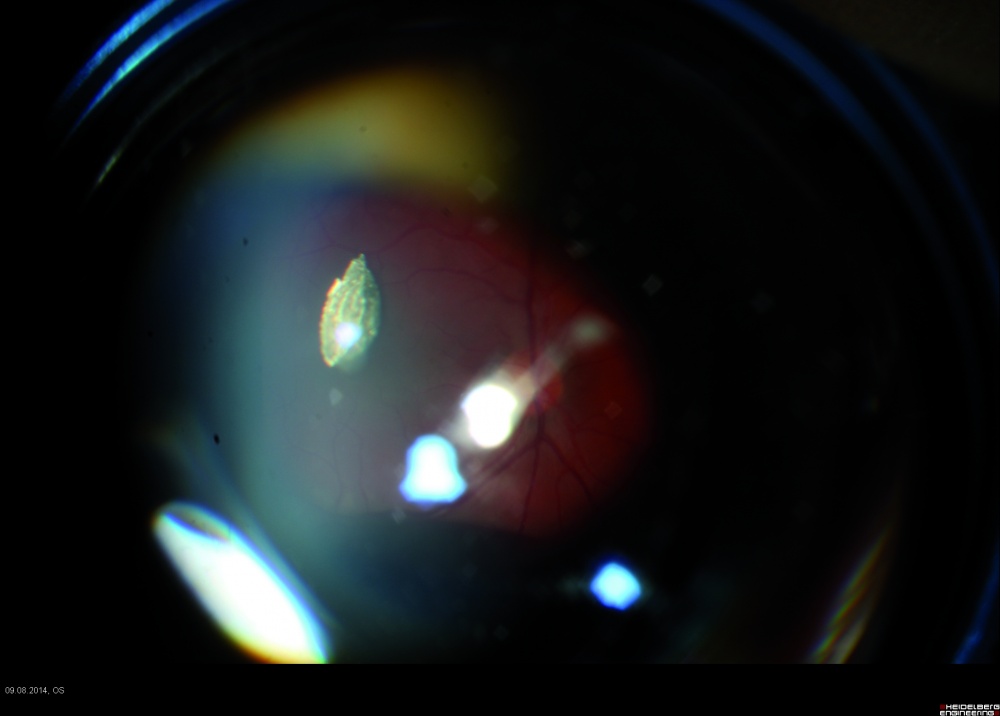

Bei der Inspektion der vorderen und hinteren Augenabschnitte zeigte sich eine zentrale 3 mm lange Penetrationsstelle der Hornhaut (Abbildung 1), eine Verletzung der vorderen und hinteren Linsenkapsel mit einer traumatischen Sekundärkatarakt (Abbildung 2) und ein im mittleren Glaskörperraum liegender metallischer Fremdkörper (Abbildung 3). Der Visus am betroffenen Auge betrug 0,2 und am Partnerauge 1,0 ohne Korrektion.

Die Ultraschalldiagnostik zeigte den klinisch (Abbildung 4) gut sichtbaren Fremdkörper im mittleren Glaskörperraum lokalisiert. Die Untersuchung des Augenhintergrundes zeigte keine Verletzung der Netzhaut. Es wurde deshalb auf eine Röntgen(CT)- Diagnostik verzichtet.

Bei unserem Fallbeispiel kam der IOFK im Glaskörper zu liegen (Abbildungen 3 – 4), ohne weitere Strukturen im hinteren Augenabschnitt verletzt zu haben. Der Fremdkörper kann aber auch in der Netzhaut, im subretinalen Raum oder intraskleral lokalisiert sein. Am häufigsten befindet er sich im Bereich des hinteren Augenpoles.